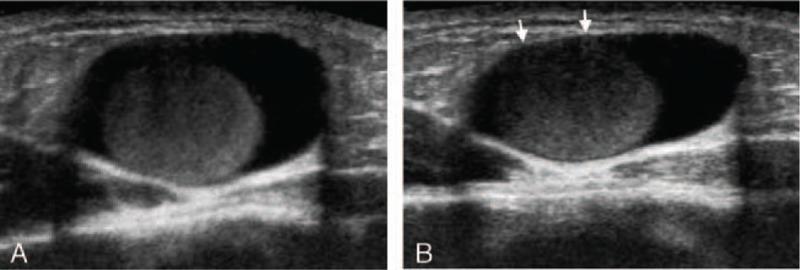

Subcutaneous bronchogenic cysts have been described rarely, particularly among adolescents. Only a few reports have described the ultrasonographic features of bronchogenic cysts, characterizing them as nonspecific cystic masses with or without internal echogenic foci or debris. Therefore, it is hard to differentiate subcutaneous bronchogenic cysts from other subcutaneous cystic tumors ultrasonographically.We report a case of presternal subcutaneous bronchogenic cyst in an 18-year-old man with unusual ultrasonographic findings. Ultrasonography revealed a small, oval, cystic mass containing a well-circumscribed, heterogeneously hypoechoic, egg-shaped lesion in the dependent portion of the mass within the subcutaneous fat layer overlying the sternum.Surgical excision was performed, and the cystic mass was diagnosed as a bronchogenic cyst. On pathological examination, the internal, heterogeneously hypoechoic, ball-like lesion was found to be mucous material within the cyst. To our knowledge, this is the first reported case of a presternal subcutaneous bronchogenic cyst presenting with a ball-like lesion inside of the cyst. This unusual ultrasonographic feature can be a clue to the diagnosis of subcutaneous bronchogenic cyst.In conclusion, if an anechoic cyst containing an internal, well-circumscribed, hypoechoic ball-like lesion is seen in the presternal subcutaneous fat layer, subcutaneous bronchogenic cyst should be considered in the differential diagnosis of subcutaneous cystic masses.

皮下支气管源性囊肿很少见,尤其是在青少年中。仅有少数报告描述了支气管源性囊肿的超声特征,将其描述为具有或不具有内部回声灶或碎屑的非特异性囊性肿块。因此,很难通过超声检查将皮下支气管源性囊肿与其他皮下囊性肿瘤区分开来。我们报告一例18岁男性胸骨前皮下支气管源性囊肿,其具有不寻常的超声表现。超声检查显示一个小的椭圆形囊性肿块,在胸骨上方皮下脂肪层内肿块的下垂部分含有一个边界清晰、不均匀低回声的椭圆形病变。进行了手术切除,囊性肿块被诊断为支气管源性囊肿。病理检查发现,内部不均匀低回声的球状病变为囊肿内的黏液物质。据我们所知,这是首例报告的胸骨前皮下支气管源性囊肿内出现球状病变的病例。这种不寻常的超声特征可作为诊断皮下支气管源性囊肿的线索。总之,如果在胸骨前皮下脂肪层中看到一个含有内部边界清晰、低回声球状病变的无回声囊肿,则在皮下囊性肿块的鉴别诊断中应考虑皮下支气管源性囊肿。